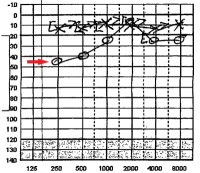

Audiogram demonstrating right-sided hearing loss. Normal, left-sided hearing is demonstrated by straight line of X’s across top of image. Right-sided hearing is represented by a series of O’s (red arrow). The drop of the line from the 10dB line is the amount of hearing lost; in this case 45dB at 250Hz and 25dB at 1000Hz & 4000Hz.